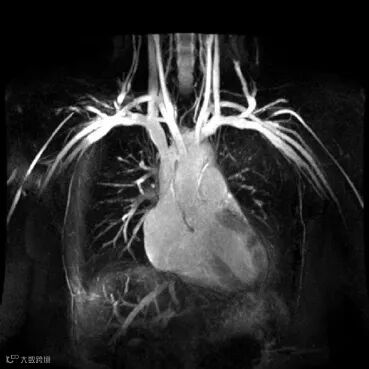

更多MRI相关的有趣话题我会在下一章介绍。这里直接抛出一张新鲜出炉的MRI图像吧:

胸部血管成像图